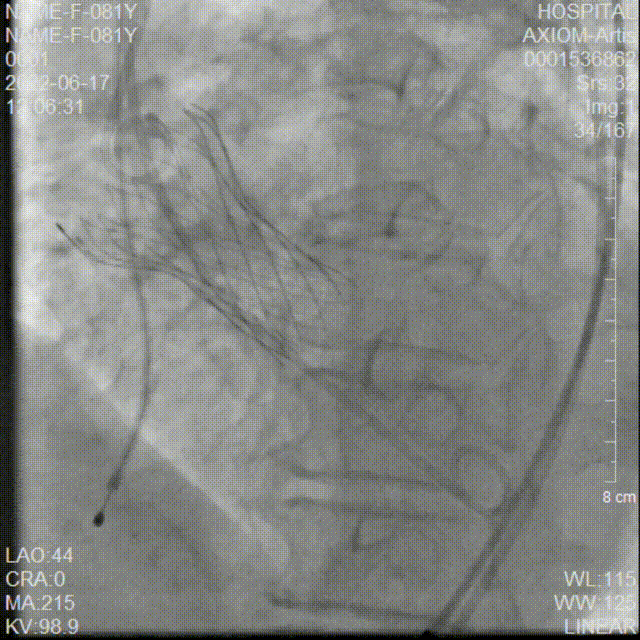

20mm球囊预扩